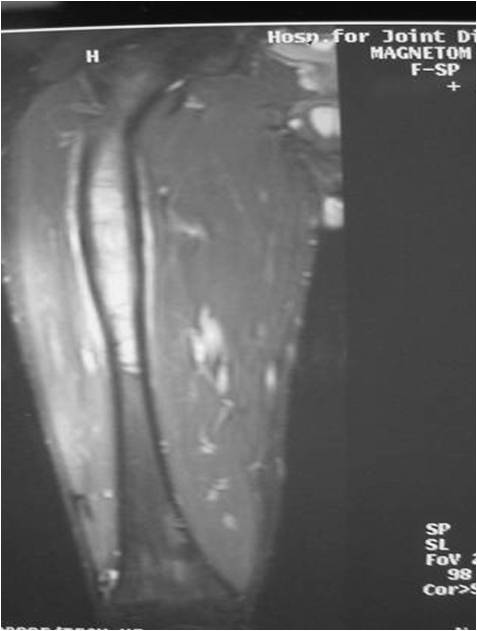

Radiographic Presentation

- Permeative or moth eaten bone destruction

- Ill defined and malignant appearing

- Bony changes are often subtle

- Soft Tissue Mass in 90% of of cases

- Periosteal Reaction in 50% of cases

- Due to irritation, edema, tumor permeation

- Onion Skin (colic pattern of irritation)

- Hair on End (rapid continuous lifting of periosteum)

- Reactive Bone Sclerosis is rare but occurs in 10% of cases

- No cartilage or bone production by tumor

- Pathologic fracture in 10-15%